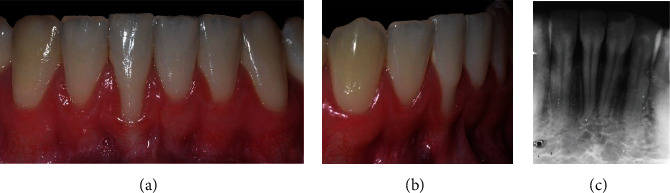

The patient, a 22-year-old Caucasian man, nonsmoker, systemically healthy, presented with the main complaint of difficulty with cleaning the region of tooth #41 and fear of losing the tooth, at the Department of Periodontology, Federal University of Pelotas (Pelotas, Rio Grande do Sul, Brazil), in April 2018. The patient had previously undergone orthodontic treatment. According to the clinical and radiographic examination, a RT2 RG was observed on the vestibular surface of the right mandibular central incisor (4 mm high and 3 mm wide at the height of the CEJ), with a probing depth (PD) of 3 mm in the proximal and 2 mm of 2 mm measured on the on free surfaces, clinical attachment level (CAL) of 6 mm on the buccal surface, radiographic interproximal bone loss mesial and distal sites, slight buccal prominence (dental linguoversion), slight dental extrusion, biofilm accumulation, protruding occlusal interference, and thin periodontal phenotype (Figure 2).

Figure 2.

Case 1. (a) Frontal view, gingival recession of 4 mm high by 3 mm wide. (b) Right lateral view. (c) Periapical radiograph, 2 mm radiographic interproximal bone loss mesial and distal.